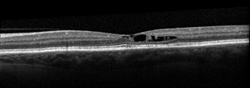

Your retina specialist also may use optical coherence tomography (OCT) to scan the retina, which may show the retinal changes commonly seen with JFT—including abnormal fluid in or under the retina (Figure 3).